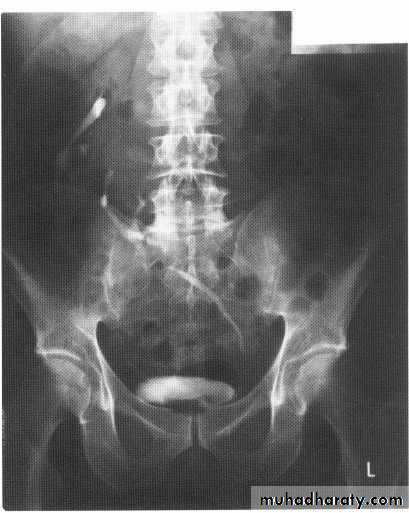

Obstructive uropathy

Causes 1.intralumenal .congenital like PUJ obstruction ,megaureter, Ureterocele (ectopic and orthotopic)Acquired : stones

Tumors (urothelial tumors )

Blood clots or sloughed papilla

2. extralumenal :abdomial or pelvic tumours

Stricture

Retroperitoneal fibrosis

Bladder outlet obstruction or bladder masses

Ivu FINDING OF ACUTE OBSTRUCTION

Increasingly dense ‘obstructive’ nephrogramModest kidney enlargement (50% of patients)

Delayed caliceal opacification

PCS and uretric dilation (g.1 mild PCS dilation ,g.2 moderate PCS dilation (blunting calyces),g.3 sever dilatation within thinning of parenchyma .

Spontaneous pyelosinus extravasations (up to 24% of patients